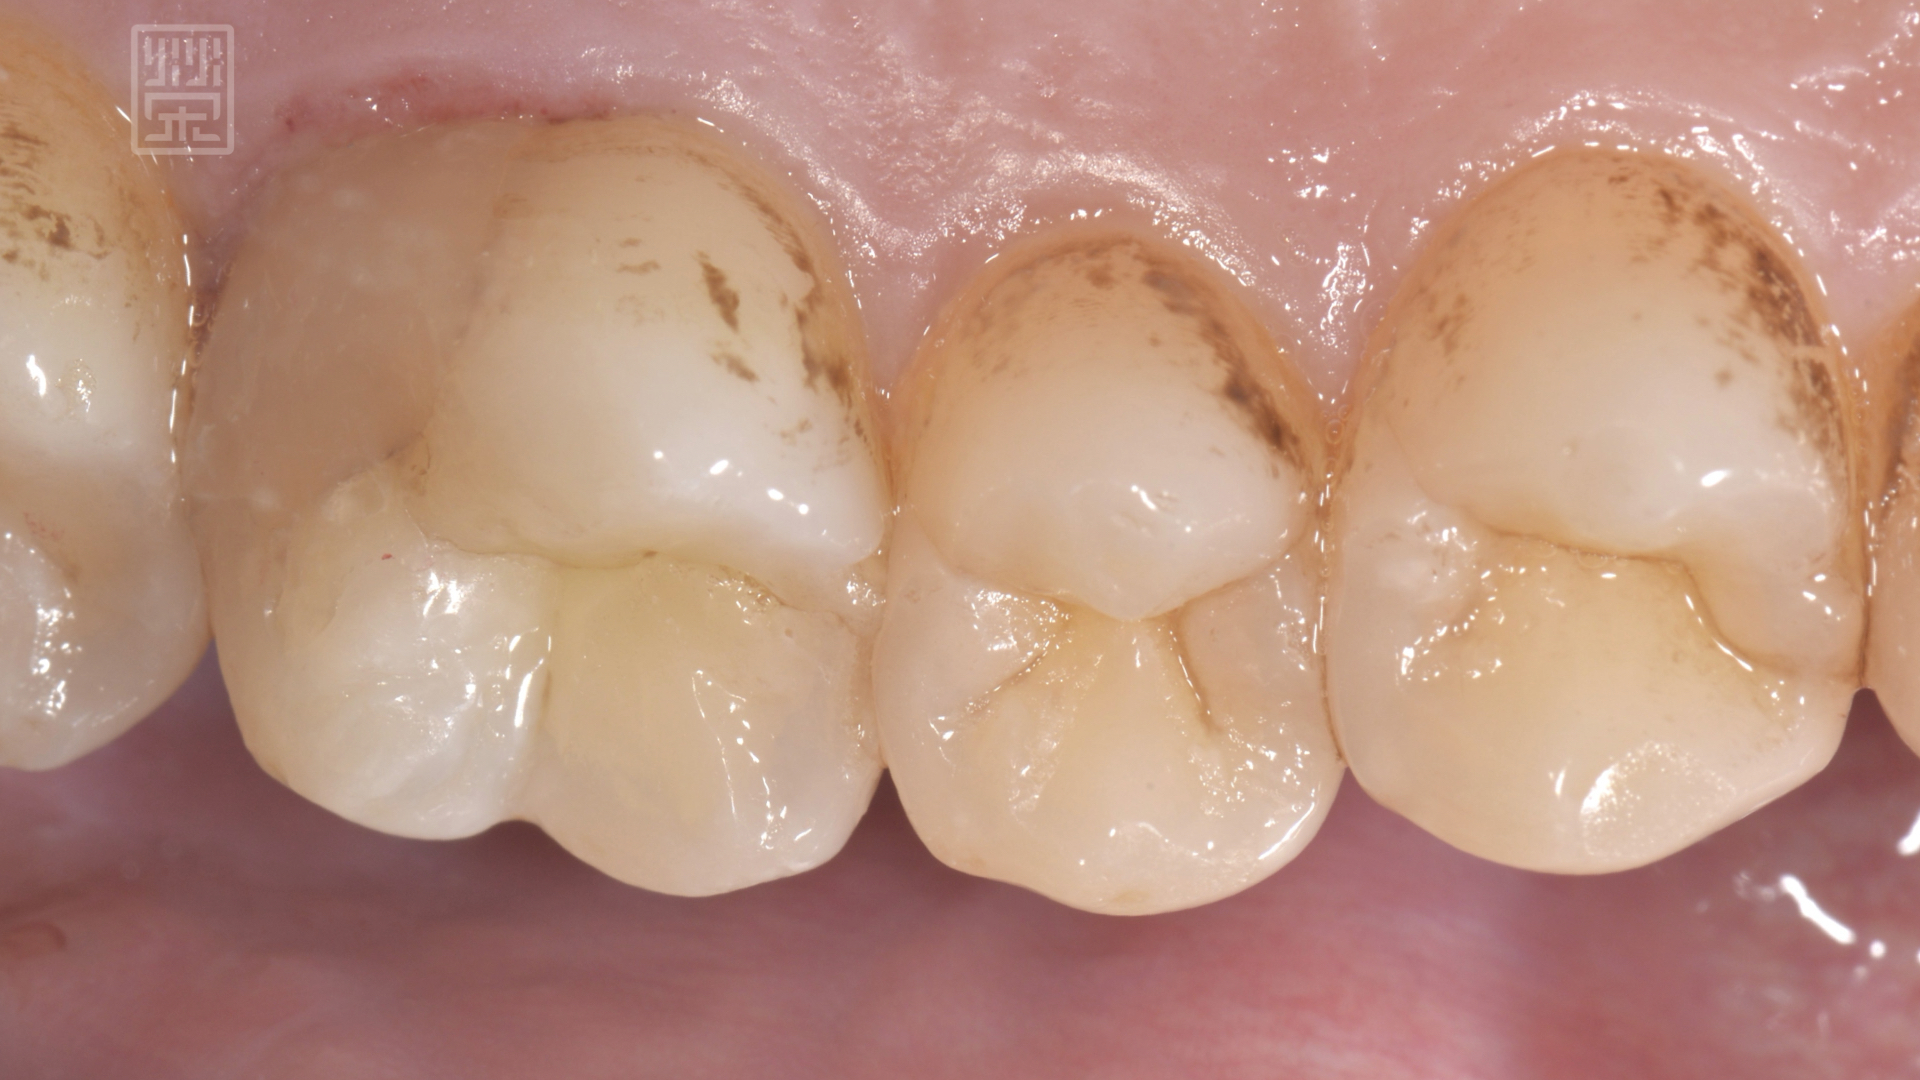

裂痕登發現牙齒有裂痕